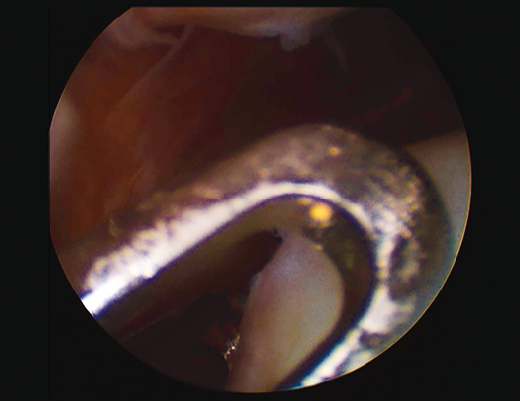

Figure 2. Arthroscopic view of an Outerbridge grade IV chronic chondral lesion of the internal femoral condyle.